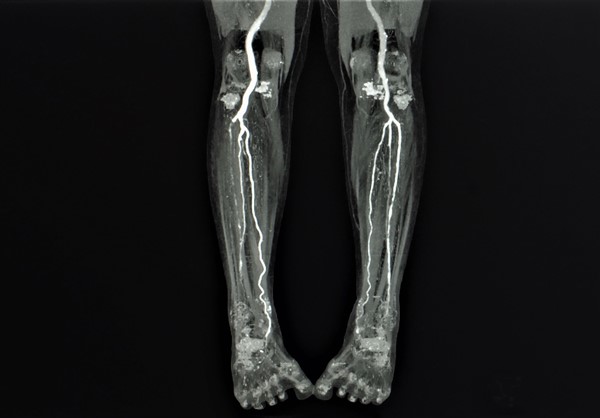

Prior to referring a patient with AU to a vascular specialist, wound clinicians may wish to consider ordering an arterial duplex ultrasound to help expedite decisions about revascularization. Other vascular imaging modalities can be ordered by the vascular specialist, if the patient is identified as a surgical candidate. See Table 4 for a comparison of imaging modalities.

-

2BGuidelines suggest duplex ultrasound imaging (DUS) as the initial arterial imaging modality to determine the presence, extent and severity of arterial disease and to help inform decisions about revascularization (Grade 2B).[5]

- Rationale: DUS provides information on the anatomic location and extent of disease as well as information about flow volume and velocity. DUS imaging is usually the first choice for vascular imaging and in some health care settings may be the only modality available. In some cases however, it may be appropriate to proceed directly to computed tomography angiography (CTA), magnetic resonance angiography (MRA) or catheter digital subtraction angiography (DSA) instead of DUS imaging.

Advantages: although DUS has been shown to be inferior to other imaging techniques such as digital subtraction angiography (DSA), DUS offers many advantages as a first-line imaging modality, including its noninvasive nature, low cost, no iodinated contrast media, no ionizing radiation, and wide availability.[5][86]

Limitations: DUS is time-consuming and highly operator dependent. Furthermore, calcification may result in an incomplete examination. DUS is also poor at estimating collateral blood supply and reserve.[5]

For patients who are candidates for revascularization, additional vascular imaging is indicated. Invasive vascular imaging (e.g. CTA, MRA, catheter angiography), should only be obtained after the decision to intervene has been made. The decision to intervene is based on history and physical examination and on the potential for improvement in quality of life, and not solely on anatomical findings.